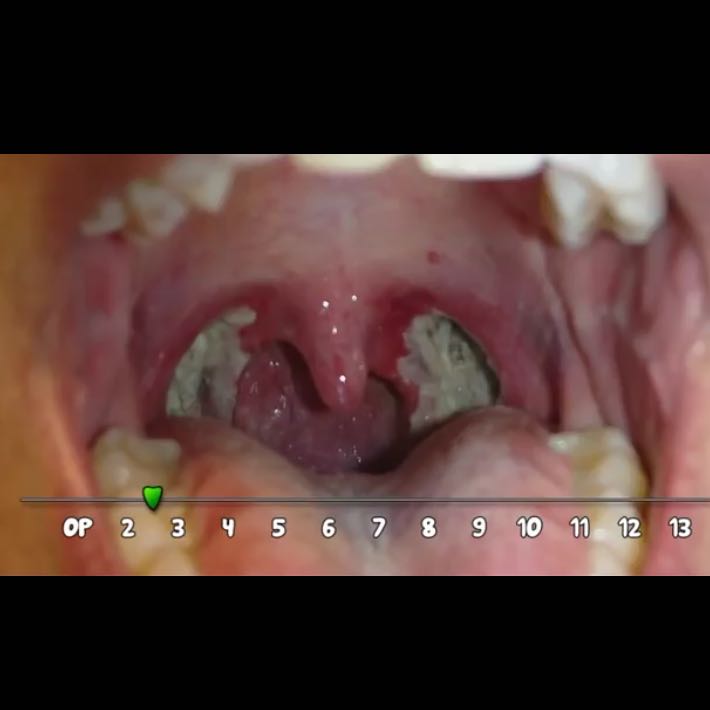

Weisse Punkte Im Rachen

Leukoplakie der Schleimhaut Tipps zur Entfernung. Zuweilen kann weißer Belag im Mund unangenehm sein, weil er von Bakterien gebildet wird, die Mundgeruch hervorrufen können. Weiße Flecken sind nicht gefährlich, können aber Beschwerden bereiten, vor allem wenn sie gleichzeitig auftreten mit: Fieber, Halsschmerzen.

Normalerweise sind diese Flecken irritierend oder schmerzhaft, und manchmal ist die pain schlimmer beim Schlucken oder beim Kontakt mit säurehaltigen Lebensmitteln In der Folge entwickeln sich Halsschmerzen, die manchmal bis in die Ohren ausstrahlen, und zu schmerzhaften Schluckbeschwerden führen Der Rachen fühlt sich rau und trocken an, oft haben die Betroffenen das Gefühl, sich räuspern oder hüsteln zu müssen